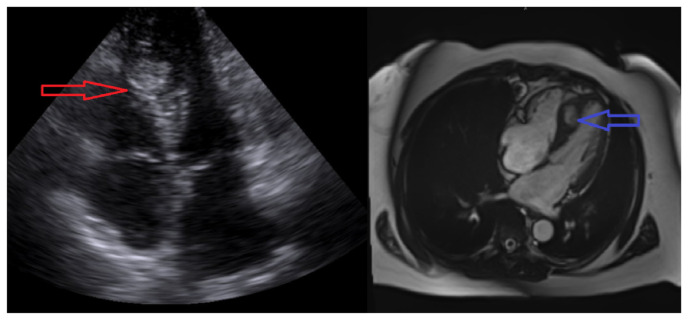

Carcinoid tumors are rare, slow-growing neoplasms of neuroendocrine origin commonly affecting the gastrointestinal or respiratory system. They metastasize to lymph nodes and the liver based on their lymphatic and venous drainage of their tissue of origin. Metastasis to the heart is exceedingly rare accounting for <2 % of cases. Exceedingly rare is the incidental detection of cardiac carcinoid metastasis as the initial presentation of carcinoid syndrome. Here, we describe a case of metastatic cardiac carcinoid detected during a routine echocardiogram done for evaluation of a systolic murmur.